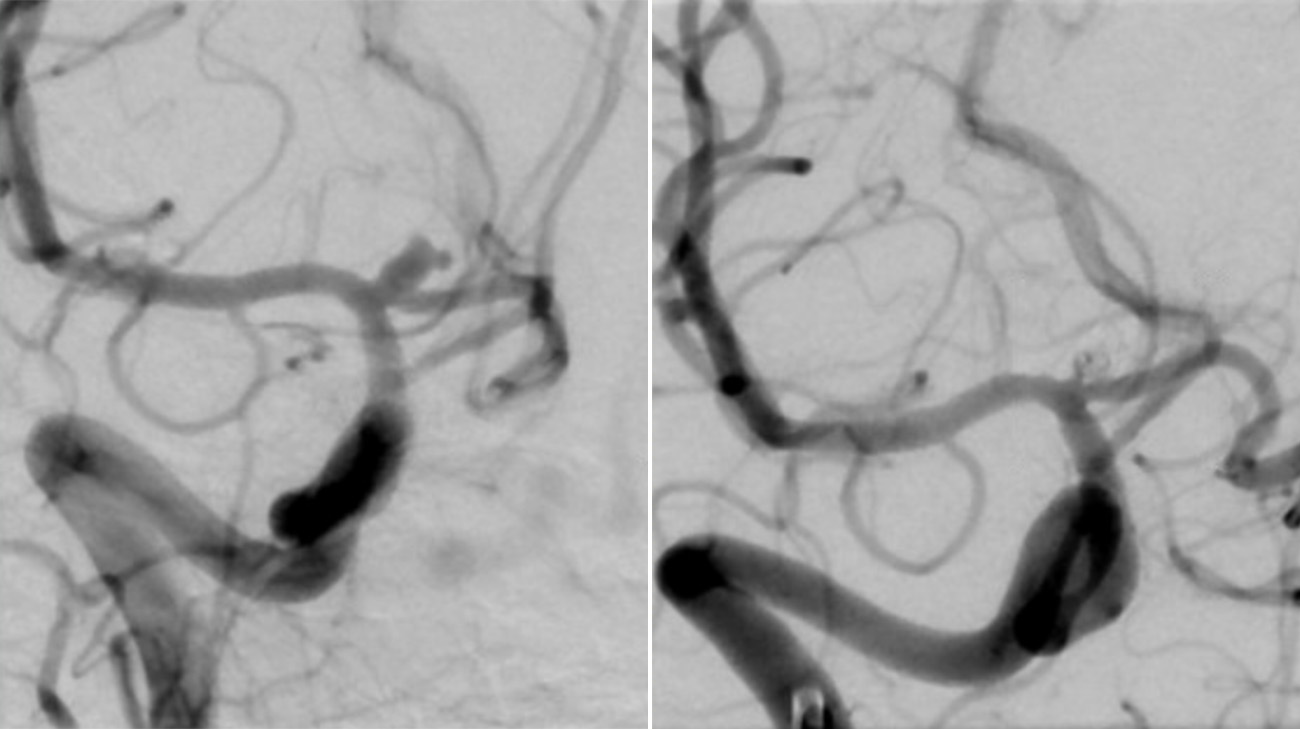

Imaging shows Julianne’s ruptured brain aneurysm before and after an endovascular coiling procedure to block blood flow into the aneurysm to prevent it from re-rupturing. (Courtesy: Cleveland Clinic)

Due to the subarachnoid hemorrhage, Dr. Moore says Julianne had increased intracranial pressure, which is a life-threatening condition that happens when there’s an imbalance between your brain tissue, cerebrospinal fluid and brain blood volume. Dr. Moore and the neurosurgery team quickly addressed this by draining excess fluid from the brain. Interventional neurologist Shazam Hussain, MD, then performed an endovascular coiling procedure to block blood flow into the aneurysm to prevent it from re-rupturing. Dr. Moore and team also worked closely with neurocritical care specialist Adam Barron, MD, and caregivers on the neuro intensive care unit to manage Julianne’s overall condition as she suffered from severe brain swelling, or cerebral edema.